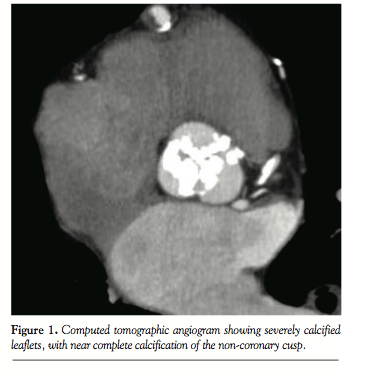

wire was still across the aortic valve, its position would not provide adequate support for further advancement of the valve. It is not entirely clear why we had difficulty crossing the valve, but review of the computed tomography angiogram was notable for significant calcification of all three coronary leaflets, with near complete calcification of the non-coronary cusp (Figure 1), so it is possible that this bulky leaflet was catching the Sapien valve, preventing advancement. Furthermore, the iliac vessels were very tortuous, therefore compromising the pushability and torquability of the delivery system from the transfemoral route.